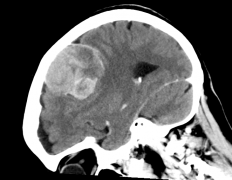

颅咽管瘤全切除有可能吗?如何避免术后复发?颅咽管瘤(cran...

晓米(化名)已经6岁了,但相对比同龄的小朋友她的个子矮了许...

儿童脑动静脉畸形手术成功率高不高? 脑动静脉畸形 是连接脑内...